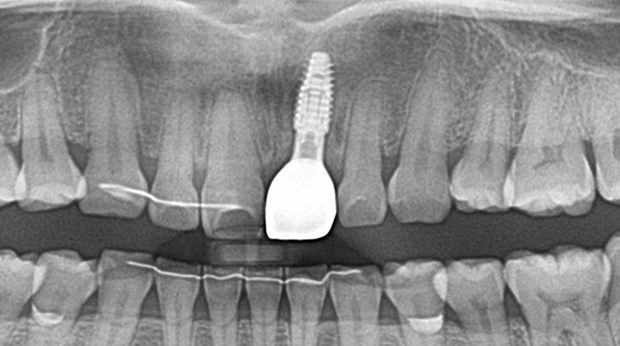

임플란트와 사랑니 발치는 외과적 시술로 잇몸을 절개하는 외과적 시술은

짧으면 짧을 수록 시술 후 붓기와 통증이 최소화됩니다.

치과의사 경력 14년차 구강외과 전문의가 빠르고 안전하게, 아프지 않게 수술해 드립니다.

치과경력 14년차 구강외과 전문의